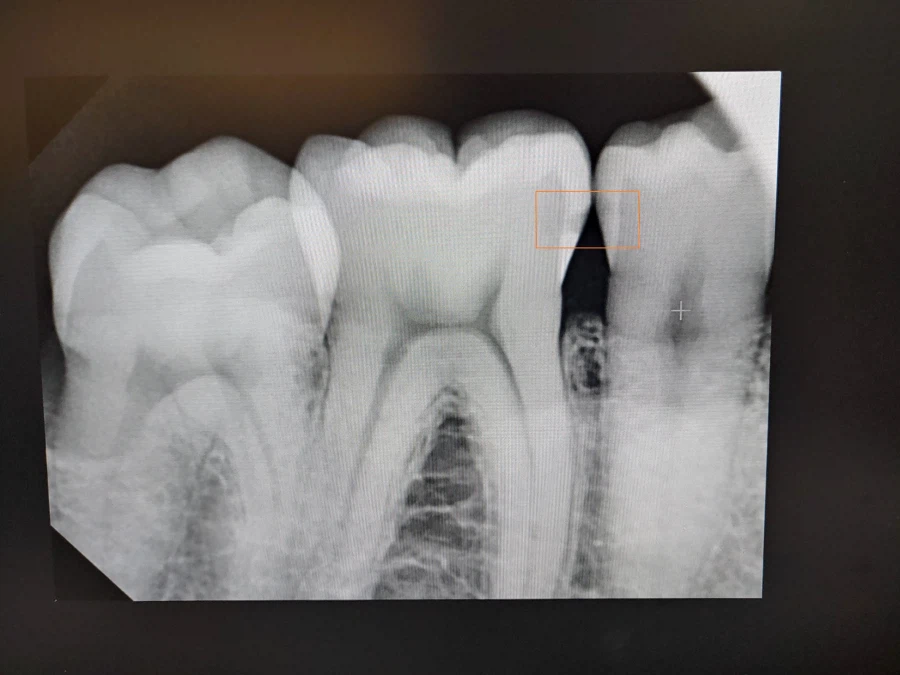

주황색 네모 안. 인접면 충치가 있는 자리. (오른쪽 하단 어금니, 46과 45 사이)

충치 통보를 받은 지 3개월이 지난 지금. X레이 사진 상으로는 충치가 거의 진행되지 않았다! 참고로 AI에게 해당 X레이 사진을 보여줬더니 인접면 충치에 대해선 언급을 하지 않았어. 오히려 주황 네모 아래쪽 잇몸을 걱정 하던데? (검게 나온 잇몸 부위)